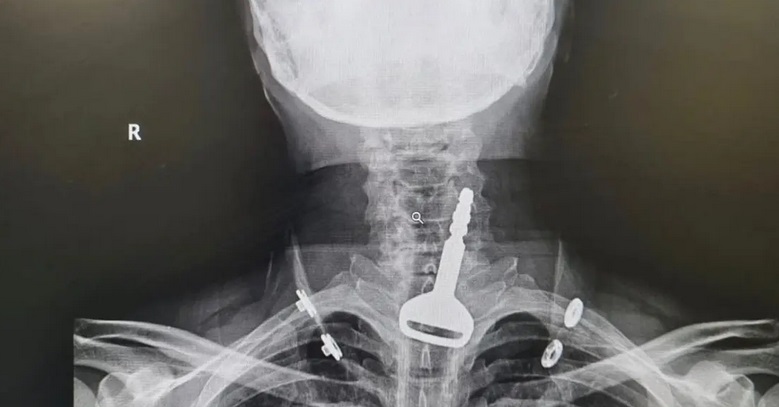

وأوضحت صحة مدينة القنفذة أن المريض، البالغ من العمر 49 عاماً، وصل لقسم الطوارئ وهو يعاني من انسداد بمجرى التنفس، ليتضح بعد الفحص السريري والأشعة وجود مفتاح سيارة عالق في القصبة الهوائية.

واعترف المريض للأطباء المعالجين بأنه ابتلع المفتاح أثناء لهوه به، ما تسبب له في حالة اختناق جزئي تطلب التدخل الجراحي عن طريق المنظار لاستخراج الجسم المعدني العالق.

وتقرر فورًا إدخال المريض قسم العمليات وتكثيف العناية الصحية له لكونه مريض قلب، وتم إجراء التدخل الجراحي عن طريق المنظار واستخراج المفتاح، ومن ثم متابعة الحالة عن طريق قسم التنويم لحين استقرار حالته الصحية وخروجه بالسلامة.